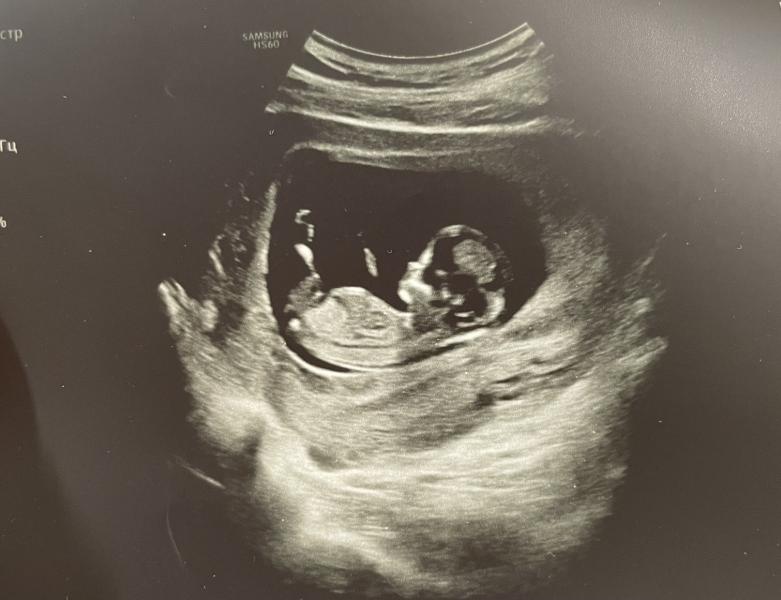

Сегодня был скрининг. По узи все в норме.🥰 Спокойствия мне придавало то, что у нас пгт сделан. А так бы волновалась сильно) Удивляет меня как при таком маленьком размере (5,4см) эмбрион уже выглядит прям как человечек!! Носик, подбородочек, лоб, губки ☺️☺️☺️ Такая милота прям))

По узи не сказали. Но я генетический тест эмбриону делала - девочка☺️